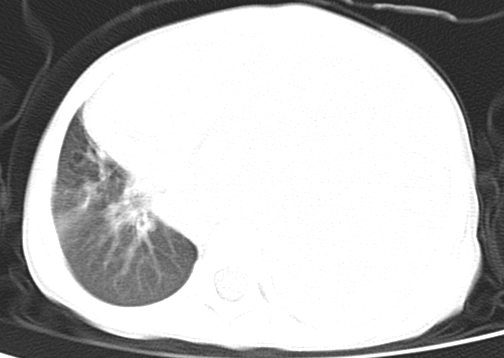

患儿 女 4岁,发热 咳嗽 胸透 考虑:左侧脓胸

左侧胸廓内见大量密实阴影,肺尖部尚有少量肺组织影,纵膈明显受压移位,肋骨未见明显受侵征象,虽然病人年龄较小,但如此大量的“积液”,还是要警惕,不同意一般感染,可结合穿刺脱落细胞学检查。

1)考虑左肺炎症感染。2)左侧大量胸腔积液。

1)考虑左肺炎症感染。2)未经穿刺只能定左侧大量胸腔积液。

左侧张力性大量胸腔积液压迫性肺不张、感染;建议治疗后复查。